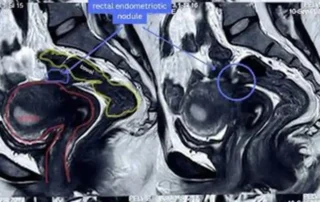

DOI: 10.36205/trocar7.2026008 - Real-Time Surgical Guidance with Robotic-Integrated Intraoperative Ultrasound in Bowel Endometriosis: A Two-Case Experience

Anshuma Shukla Kulkarni, Anushka Mehta, Riyanshi Thakur

Real-Time Surgical Guidance with Robotic-Integrated Intraoperative Ultrasound in Bowel Endometriosis: A Two-Case Experience

DOI: 10.36205/trocar7.2026009